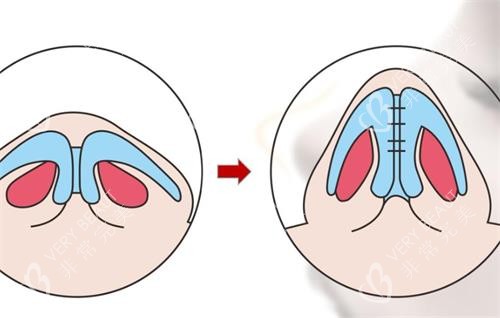

手术过程

手术当天,医院的工作人员都非常热情和贴心,让我紧张的心情得到了较大的缓解。进入手术室后,麻醉师为我进行了麻醉,整个手术过程我没有感觉到任何疼痛。李振医生的操作非常熟练,每一个步骤都严谨细致。虽然我在麻醉状态下,但后来听护士说手术进行得很顺利,用时也比预期的要短一些。